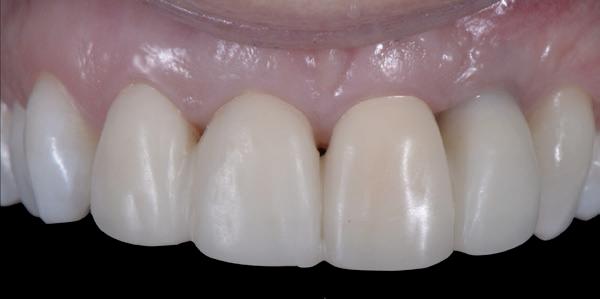

De flap en graft worden met poly-propelene 6.0 hechtingen gefixeerd. De tijdelijke reconstructie wordt herplaatst (foto 17-20).

Na 4-6 weken kan het aangebrachte healing abutment worden vervangen door een tijdelijk abutment. Deze wordt aan de kunststof reconstructie verbonden om zo de gingiva ter plaatse van de 22 te vormen. Zo lijkt het of er geen implantaat maar nog steeds een wortel aanwezig is, wat het esthetisch eindresultaat ten goede zal komen (foto 21-23). Vanaf 4-6 maanden ziet het weefsel er gezond uit. Nu kan met de uiteindelijke restauratiefase worden gestart (foto 24 en 25).

Er wordt een afdruk of een intra-orale scan genomen van de situatie met tijdelijke voorzieningen en de geprepareerde situatie. Ook mag een portretfoto en mondfoto niet ontbreken. Al deze informatie gaat naar het laboratorium zodat de onderstucturen van de restauraties gemaakt kunnen worden (foto 26).

De vier restauraties worden in samenspraak met de ceramist en de patiënt gecustomized. Op dit moment kunnen er nog details worden aangepast om zo het mooiste eindresultaat te behalen.

Bij de evaluatie van deze casus blijkt dat het herstellen van de processen alveolaris ter plaatse van de 22 is gerealiseerd en dat de gingiva qua positie en volume rond de 22 en 23 is verbeterd. Het implantaat is goed ge-osseointegreerd en de gingiva rond het implantaat heeft een natuurlijke vormgeving gekregen. De kronen zijn met moderne technologie en esthetisch hoogwaardig vervaardigd door het Oral Design Center Holland. Met dank aan Eric van der Winden.

De dentale mediaanlijn is rechtop gezet, maar staat niet helemaal gelijk met de faciale mediaan. Echter, mevrouw is functioneel en esthetisch naar tevredenheid afbehandeld (foto 27-30).